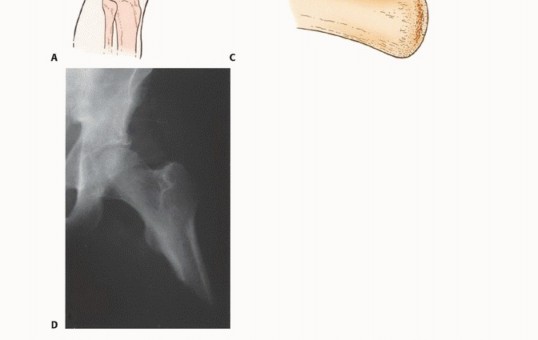

- الأشعة السينية (Plain Radiography): غالبًا ما توفر الأشعة السينية أول إشارة للحاجة إلى البتر وتقدير مبدئي لمستوى البتر المطلوب. يمكن أن تكون الصور العرضية لعظم الفخذ والساق مفيدة في إظهار انتشار الورم ومدى تدمير العظام. ومع ذلك، قد لا تظهر النتائج الإشعاعية إلا بعد تدمير ما يصل إلى 30% من بنية العظم.

- التصوير المقطعي المحوسب (CT) والتصوير بالرنين المغناطيسي (MRI): تعتبر هذه التقنيات الأكثر فائدة في تحديد مستوى انتشار الورم داخل النخاع العظمي ومدى انتشاره خارج العظم، وهو ما يستخدم لتحديد مستوى البتر. يُعد التصوير بالرنين المغناطيسي أيضًا مفيدًا لإظهار انتشار الورم في الهياكل العصبية الوعائية، مما يستدعي البتر غالبًا. كما أنه الدراسة التصويرية الأكثر موثوقية في تحديد وجود النقائل القافزة (skip metastases)، والتي قد تغير مستوى البتر.

- تصوير الأوعية الدموية (Angiography والدراسات الأخرى): يعتبر تصوير الأوعية الدموية مفيدًا في تحديد مدى سالكية الأوعية الدموية الرئيسية. في كبار السن، غالبًا ما يكون الشريان الفخذي السطحي مسدودًا.